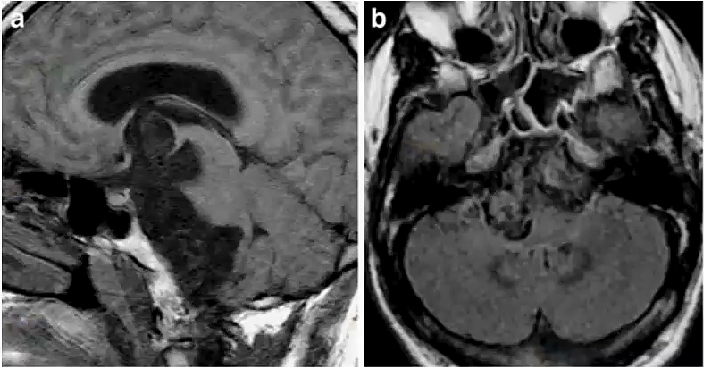

表皮样囊肿

□ CPA第三常见占位,1/2颅内表皮样囊肿位于CPA

□ 囊肿层状角质化上皮缓慢脱屑产生病变,包裹神经和血管,见缝就钻

□ MRI表现:

>T1WI 液体样低信号,>脑脊液

>T2WI 高信号,难与蛛网膜囊肿区分

● T2 FLAIR:等一高混杂信号/同CSF

● DWI:高信号,ADC受限/同CSF,术后随访确认残留